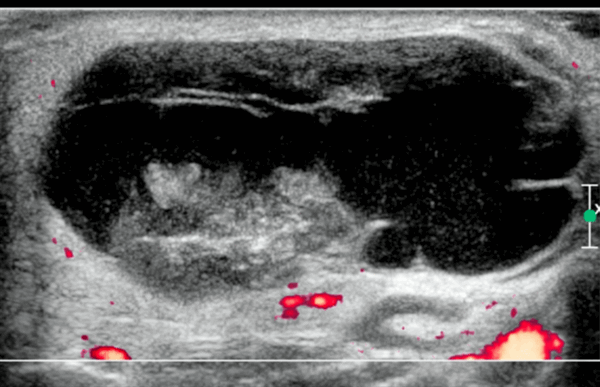

- Цветной допплер: видные внутропухолевые (при небольших солидных опухолях) и перегородочные (могут поражать) сосуды.

- Микрососудистая сонография: усиление центрального ± периферического микрососудистого кровотока.